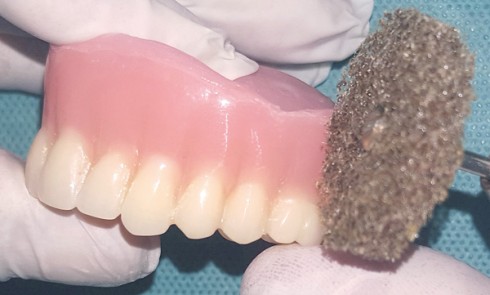

Article réservé à nos abonnés Prise en charge prothétique d’un enfant atteint d’une dysplasie ectodermique hypohidrotique

La dysplasie ectodermique est une génodermatose héréditaire liée au chromosome X qui comprend toute une série d’anomalies du développement et...